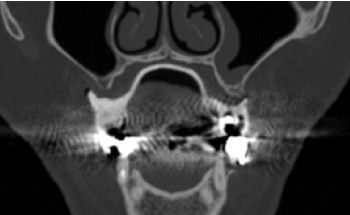

Los implantes subperiósticos son un tipo de implante dental que se coloca debajo de la encía pero por encima del hueso maxilar o mandibular. A diferencia de los implantes convencionales, que se insertan directamente en el hueso, los implantes dentales subperiósticos no requieren injertos óseos previos, lo que los hace una opción atractiva para aquellos pacientes con hueso insuficiente o que han padecido enfermedades periodontales.

En cuanto a su colocación, el procedimiento de implantación subperióstico es relativamente sencillo. Tras aplicar anestesia local, el implantólogo realiza una pequeña incisión en la encía para exponer el hueso. A continuación, introduce el implante en la zona y sutura la encía alrededor de éste. Tras el periodo de cicatrización, se coloca la corona definitiva sobre el implante.